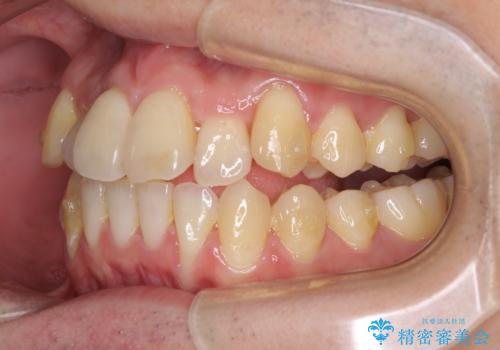

前歯のクロスバイト インビザラインによる矯正治療

- 上下のクロスバイトと前歯のデコボコを気にして来院された患者様です。

インビザラインを用い、IPR(歯と歯の間を削る)と歯列全体を拡大させることで、歯並びを整えていくこととしました。

奥に位置していた上の前歯が下の前歯を乗り越える際、奥歯でものを咬むことができず、辛い時期が続きました。